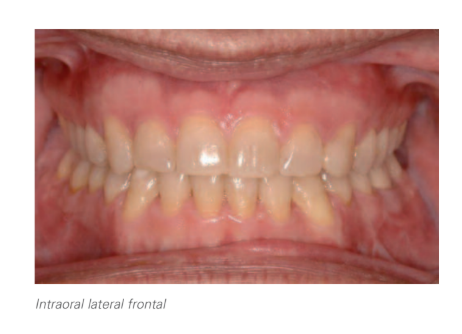

3. Análisis intraoral

- Desviación de la línea media inferior hacia la izquierda 2,5 mm de causa ósea (alteración de la morfología y tamaño del cóndilo izquierdo).

- Inclinación del plano oclusal anterior y posterior.

- Compensaciones dentoalveolares a la asimetría en ambas arcadas:

- Primer y tercer cuadrantes con torque corono lingual excesivo (a excepción del 38 que presenta una torsión corono vestibular acusada).

- Segundo y cuarto cuadrantes con torque corono vestibular acusado, siendo más marcado a nivel del 48.

- Resalte canino derecho aumentado. Resalte canino izquierdo disminuido.

- Mordida cruzada de 18-48 y 28-38.

- Resalte: 2,5 mm.

- Discrepancia óseo-dentaria positiva en ambas arcadas.

- Discrepancia de Bolton superior por defecto maxilar.

- Lado derecho: Clase III molar y Clase I canina.

- Lado izquierdo: Clase I molar y canina.

- Sobremordida: 2 mm.